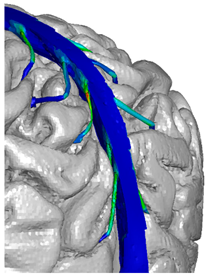

| Frontal veins | ![]() | ![]() | ![]() |

| Parietal veins | ![]() | ![]() | |

| Occipital veins | ![]() | ![]() |